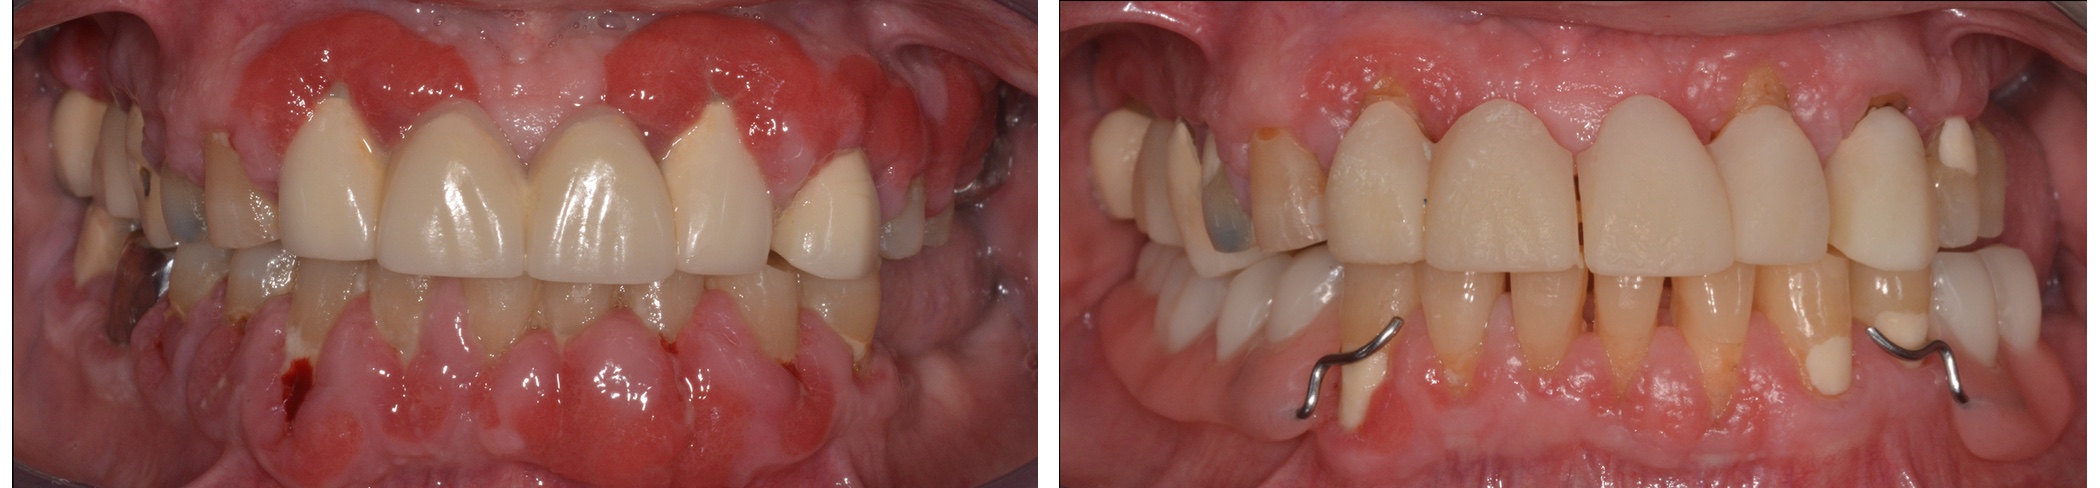

A fogágybetegség kialakulásához sok esetben hozzájárul egy nem megfelelően elkésztett tömés, korona vagy híd.

Annak érdekében, hogy a fogágyat és az ínyt kezelni tudjuk és gyulladásmentes állapotba hozzuk, szükséges ezek eltávolítása, ideiglenes pótlással történő helyettesítése.

A megfelelő végleges pótlás elkészítéséhez, a fogágy és implantátum körüli csont és íny gyógyuláshoz fontos a jól elkészített ideiglenes pótlás, mely az esztétikát és rágófunkciót is helyreállatja.